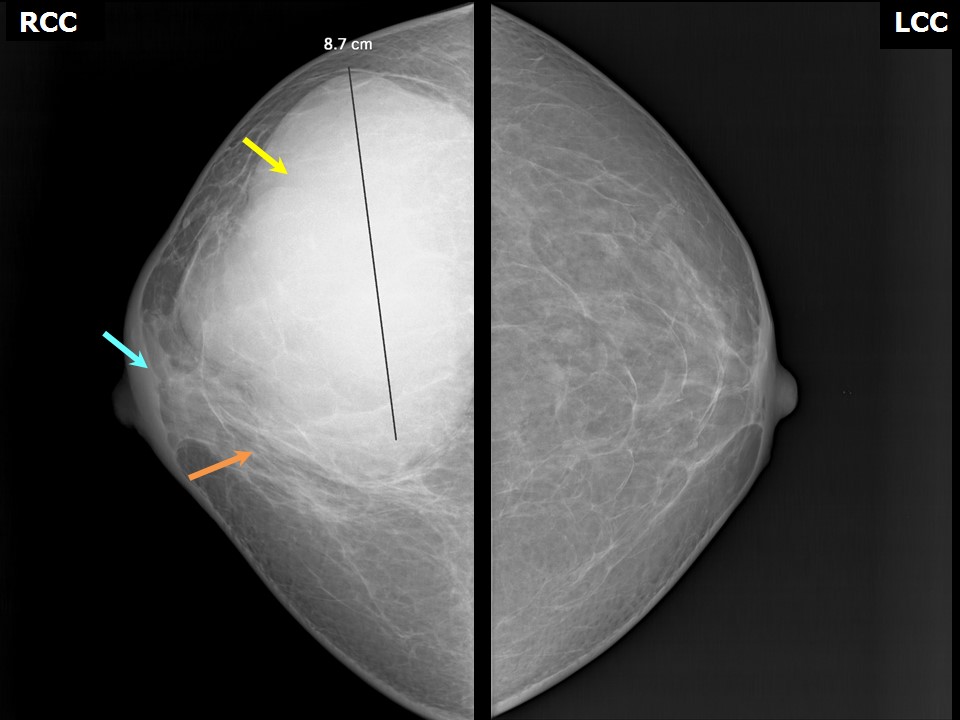

Феномен гипердиагностики в маммографии: примеры и иллюстрации

Раздел: Образы вокруг